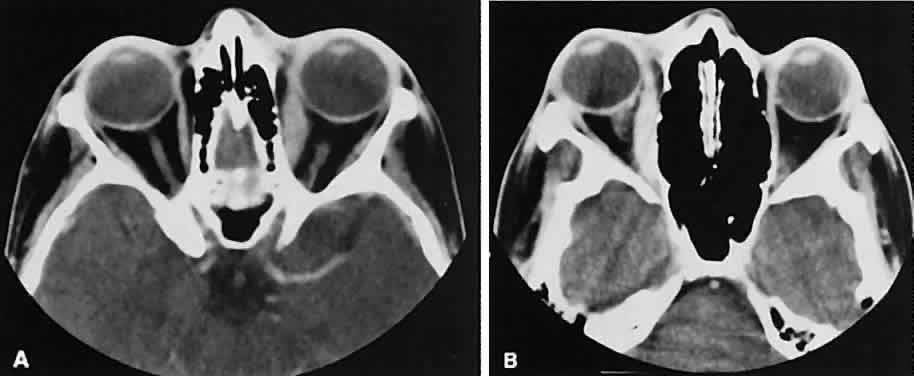

The vascular tumors under consideration are capillary hemangioma, cavernous hemangioma, lymphangioma, and hemangiopericytoma. Capillary hem-angiomas and lymphangiomas are benign infiltrativetumors seen in a pediatric population. Capillary hemangiomas have a homogeneous consistency, display intense uniform contrast enhancement, and do not usually displace any orbital structures (Fig. 12). Phleboliths are a characteristic finding in hemangiomas and, when present, are virtually pathognomonic of this diagnosis.56

Fig. 12. A. Axial view shows an exuberant homogenous soft-tissue mass infiltrating the retrobulbar space and periorbital tissue, typical of large infantile capillary hemangioma. B. Extension (arrow) into the adjacent periorbital tissues can be seen on the coronal view.

Lymphangiomas have a cystic component, which, on occasion, may hemorrhage into itself, accounting for rapid onset of symptoms and clinical/radiographic evidence of mass effect (Fig. 13). In all likelihood, scans require sedation for an adequate study. Thin (1.5-mm) axial views with computer reformatting for coronal views along with contrast enhancement should provide an adequate study.

Fig. 13. Axial view of a lymphangioma that shows a large mixed-density mass with a cystic component.

Both cavernous hemangiomas (Fig. 14) and hemangiopericytomas typically are seen in adults. Their radiographic appearance is similar and shows a well-demarcated, contrast-enhancing mass, although more intense enhancement may be seen with the hemangiopericytoma. The differential diagnosis of a well-demarcated, contrast-enhancing lesion is listed in Table 3.

Fig. 14. Axial (A) and coronal (B) views of a cavernous hemangioma depicted as a hyperdense-enhancing, well-circumscribed mass.